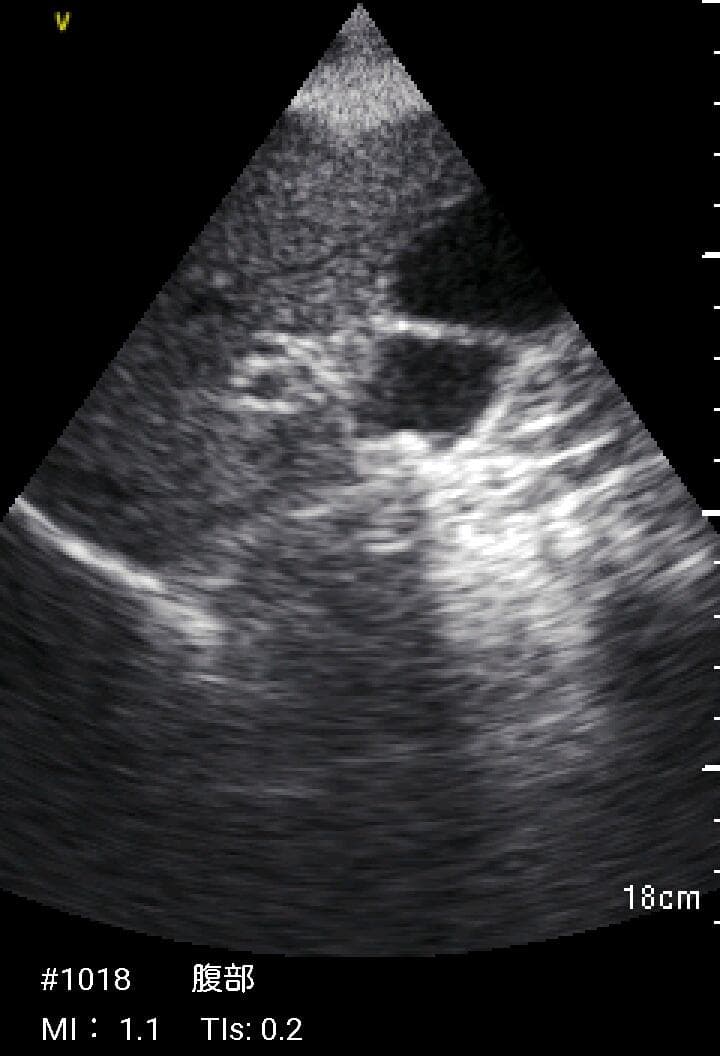

おわかりになる方のみの購入をお願いいたします実際に実施した写真をあげました正常肝臓、胆石症、頸動脈プラーク、同じく頸動脈プラーク、Mrの収縮期、同じくM弁の開放期とA弁の開放期、腹部大動脈瘤、正常の頸動脈、甲状腺右葉の結節、前立腺肥大画像の描出は条件によりますがご検討をお願いいたします経年変化、使用に伴うスレや傷などがあります機能に問題はありませんスキャンは心血管、腹部、体表に対応します外部接続端子のカバーが一部壊れていますが蓋は閉まりますバッテリーはフル充電されますが劣化はあると思います医療用モニタリング機器 Vscan Extend、GE- モデル名: Vscan Extend- ブランド: GE- 色: ホワイト- 機能: 医療用モニタリング機器ご覧いただきありがとうございます。。[新品未使用品]KT TAPE ブラック 25cm プレカット 150枚入